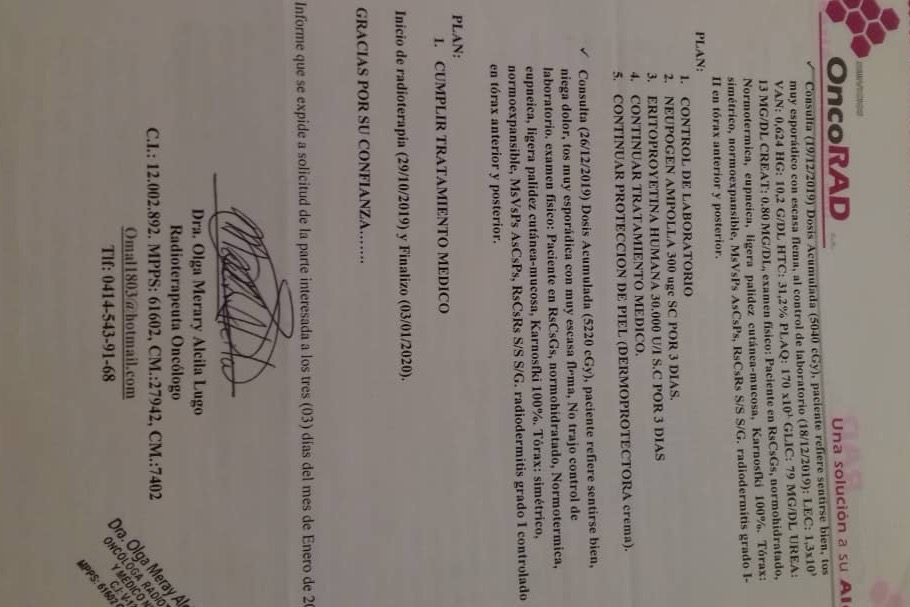

En septiembre de 2019 fue diagnosticada con cáncer de pulmón con una Lesión Ocupante de Espacio (LOE) de 2,5 cm y otra lesión en el Mediastino de 5,4 x 4,7 cm.

A través de varios familiares hemos logrado conseguir dinero para realizarle 36 ciclos de radioterapia y 6 de quimioterapia, además del tratamiento y todos los medicamentos requeridos hasta ahora, logrando una reducción importante del tamaño del tumor en pulmón en 40 %. Gracias a Dios la lesión en el mediastino se redujo también en un 80%.

A continuación les dejo el diagnóstico, los exámenes, y los presupuestos de los próximos exámenes que hay que hacerle a mi mamá.

In September 2019, she was diagnosed with lung cancer with a Space Occupying Injury (LOE) of 2.5 cm and another lesion in the Mediastinum of 5.4 x 4.7 cm.

Through several family members we have managed to raise money to perform 36 cycles of radiotherapy and 6 of chemotherapy, in addition to the treatment and all the medications required so far, achieving a significant reduction in the size of the tumor in the lung by 40%. Thank God the injury to the mediastinum was also reduced by 80%.

Down here I leave the diagnosis, exams, and budgets for the next exams to be done to my mom.